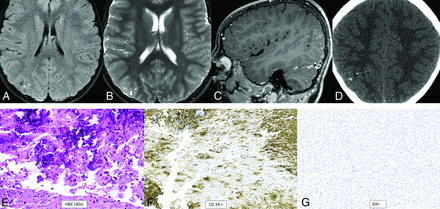

Polymorphous low-grade neuroepithelial tumor of the young. It is a cortical/subcortical mass on T2-FLAIR (A) and T2-weighted images (B) with a cystic (“bubbly”) appearance, some suppression of fluid signal on the FLAIR image, and faint heterogeneous enhancement (C) within the right inferior parietal lobule (arrows). CT shows faint specks of calcification within the lesion (D). Histology demonstrates a relatively well-demarcated low-grade neuroepithelial tumor with prominent dystrophic calcification (E). Tumor cells have oligodendroglial-like morphology and are strongly positive for CD34 (F), with low proliferative activity. Immunohistochemical stain is negative for IDH1 R132H (G) and positive for OLIG2. Chromosomal microarray identified loss of 10q21.3q26.13 disrupting CTNNA3 and FGFR2, representing a FGFR2-CTNNA3 fusion.

Polymorphous low-grade neuroepithelial tumor of the young is another of the 4 types of pediatric low-grade tumors and is definitionally WHO grade 1.1 It is a glial tumor with oligodendrocytic features, frequent calcifications, and an infiltrative growth pattern. It is characterized by strong CD34 immunostaining and mitogen-activated protein kinase (MAPK) pathway alterations, specifically involving FGFR or BRAF.18 The most specific alteration appears to be FGFR2-CTNNA3 fusion.16 The median age at diagnosis is 15.5 years (range, 5–57 years), with a slight female predominance (male/female ratio, 1:1.7), and epilepsy is the most common presentation (87%).19 The tumor is located supratentorially, almost always cortically or subcortically, with two-thirds in the temporal lobe. Prominent dense calcifications are classic, with calcifications occurring in 83% of cases. Typical tumors are well-circumscribed, solid, and cystic, T1- and T2-signal variable, T2-FLAIR hyperintense, and nonenhancing or mildly enhancing (Fig 2).19